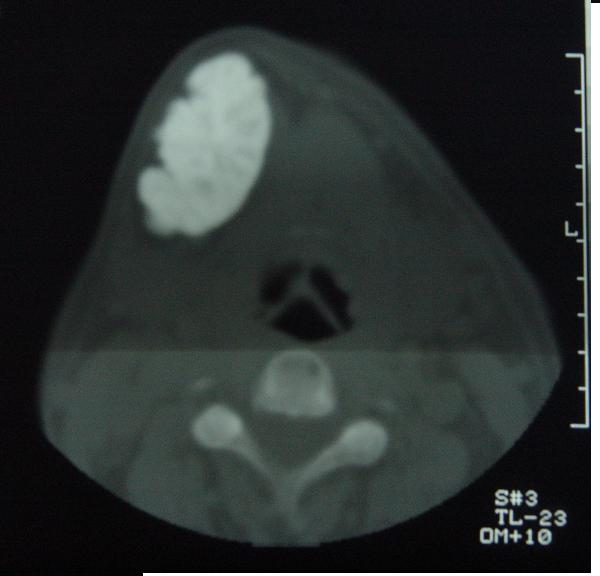

标题: CT12465:下颌骨肿瘤,请会诊 [打印本页]

标题: CT12465:下颌骨肿瘤,请会诊

发现下颌骨肿瘤近30年.逐渐增大.

考虑右侧下颌骨水平部及升部骨纤维异常增殖症可能性大。

考虑右侧下颌骨骨化性纤维瘤。